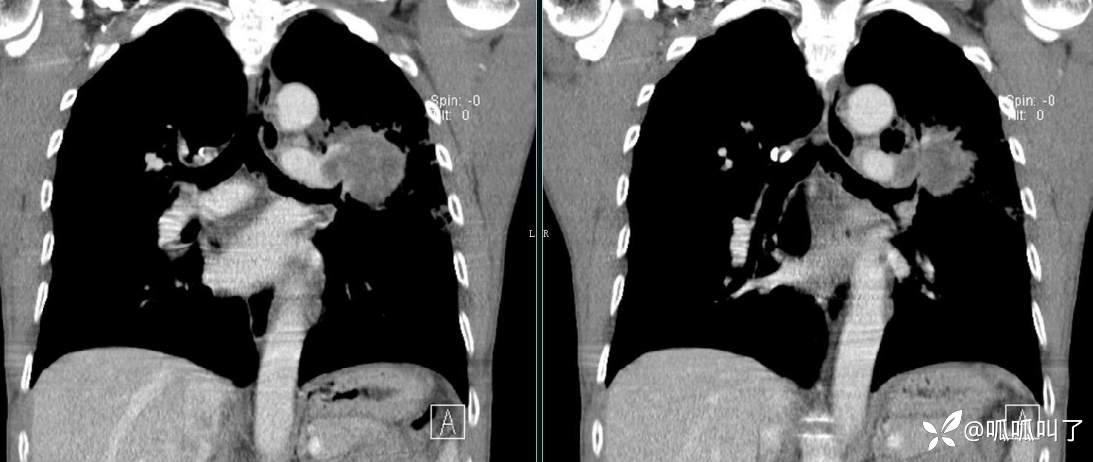

胸部CT平扫和增强: